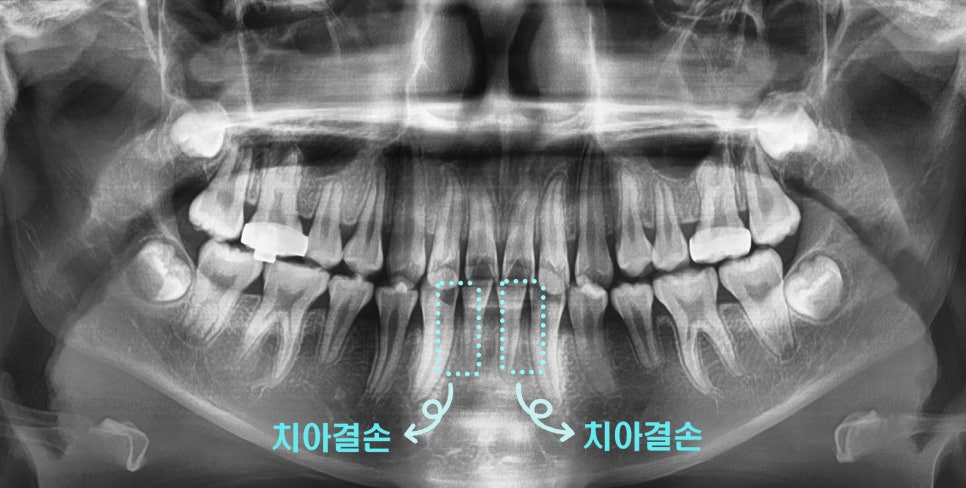

이번 케이스는

‘위턱이 많이 나온 상황’으로

측절치의 결손으로

위턱과 아래턱의 부조화가 나타났습니다.

이를 해결하려면,

위턱을 뒤로 밀어 넣어야 했기 때문에

헤드기어 를 활용해 교정을 진행하기로 했습니다.

구강 검진을 통해서 치아 개수가 정상인지?

체크하는 게 좋습니다.